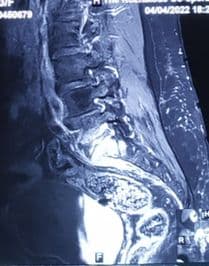

Infective Spondylodiscitis at L5-S1

A 65-year-old female presented with severe low back pain that had been progressively worsening over several weeks, resulting in significant difficulty in ambulation and restriction of daily activities. Clinically, she exhibited localized tenderness in the lumbosacral region with painful spinal movements. Her condition raised strong suspicion of an underlying spinal infection. Subsequent laboratory investigations revealed elevated inflammatory markers, supporting an infective etiology.

Imaging studies, including MRI and plain X-rays, confirmed the presence of spondylodiscitis at the L5-S1 level, characterized by destruction of the vertebral end plates and narrowing of the intervertebral disc space. There were also early signs of instability at the lumbosacral junction. The progressive bony destruction was concerning, as it posed risks of persistent pain, deformity, and potential neurological compromise if left untreated. The combination of advanced age, severe functional disability, and the destructive changes necessitated surgical management. A plan for posterior instrumentation with stabilization, debridement, and bone grafting was made to control infection, restore stability, and promote fusion.